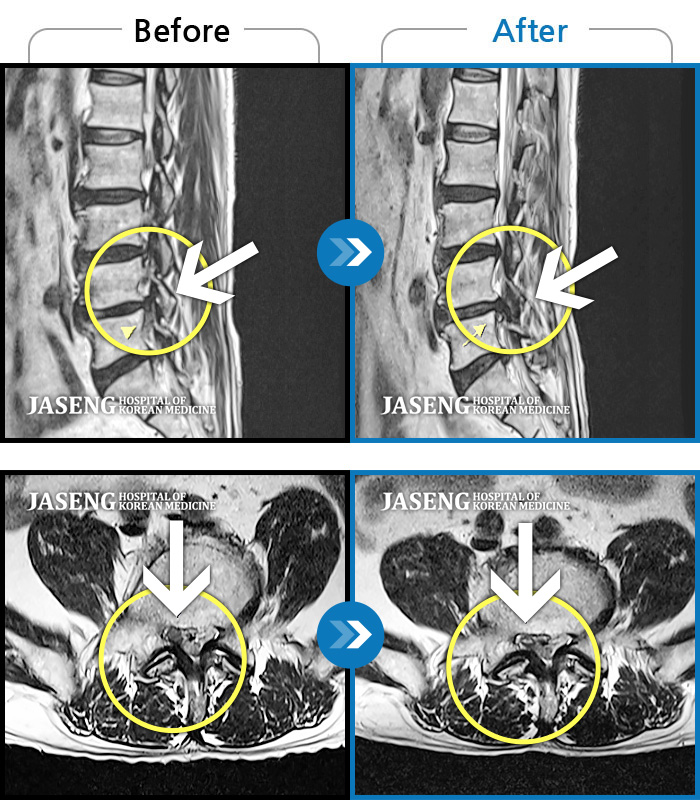

허리디스크

광주 · 김동은 원장

양측 허리부터 양측 골반까지 당기는 통증, 양측 하지 후면으로 이어지는 통증

촬영시기

2022.09.05 ~ 2024.05.06

2024.05.24